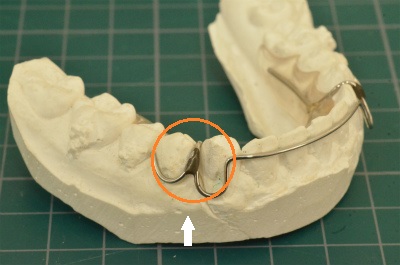

固定式リテーナー (当院では主に下顎の前歯部に使用)

⑧ 固定式リテーナーは着けっぱなしで楽だけどデンタルフロスを通せない・・

当院ではかつてはプレートタイプのリテーナーを選んでいたのですが、長期間にわたる保定具合(特に下顎の前歯)に難があることから上顎には主にマウスピースタイプのクリアリテーナー、下顎には主に固定式リテーナーを採用しております。